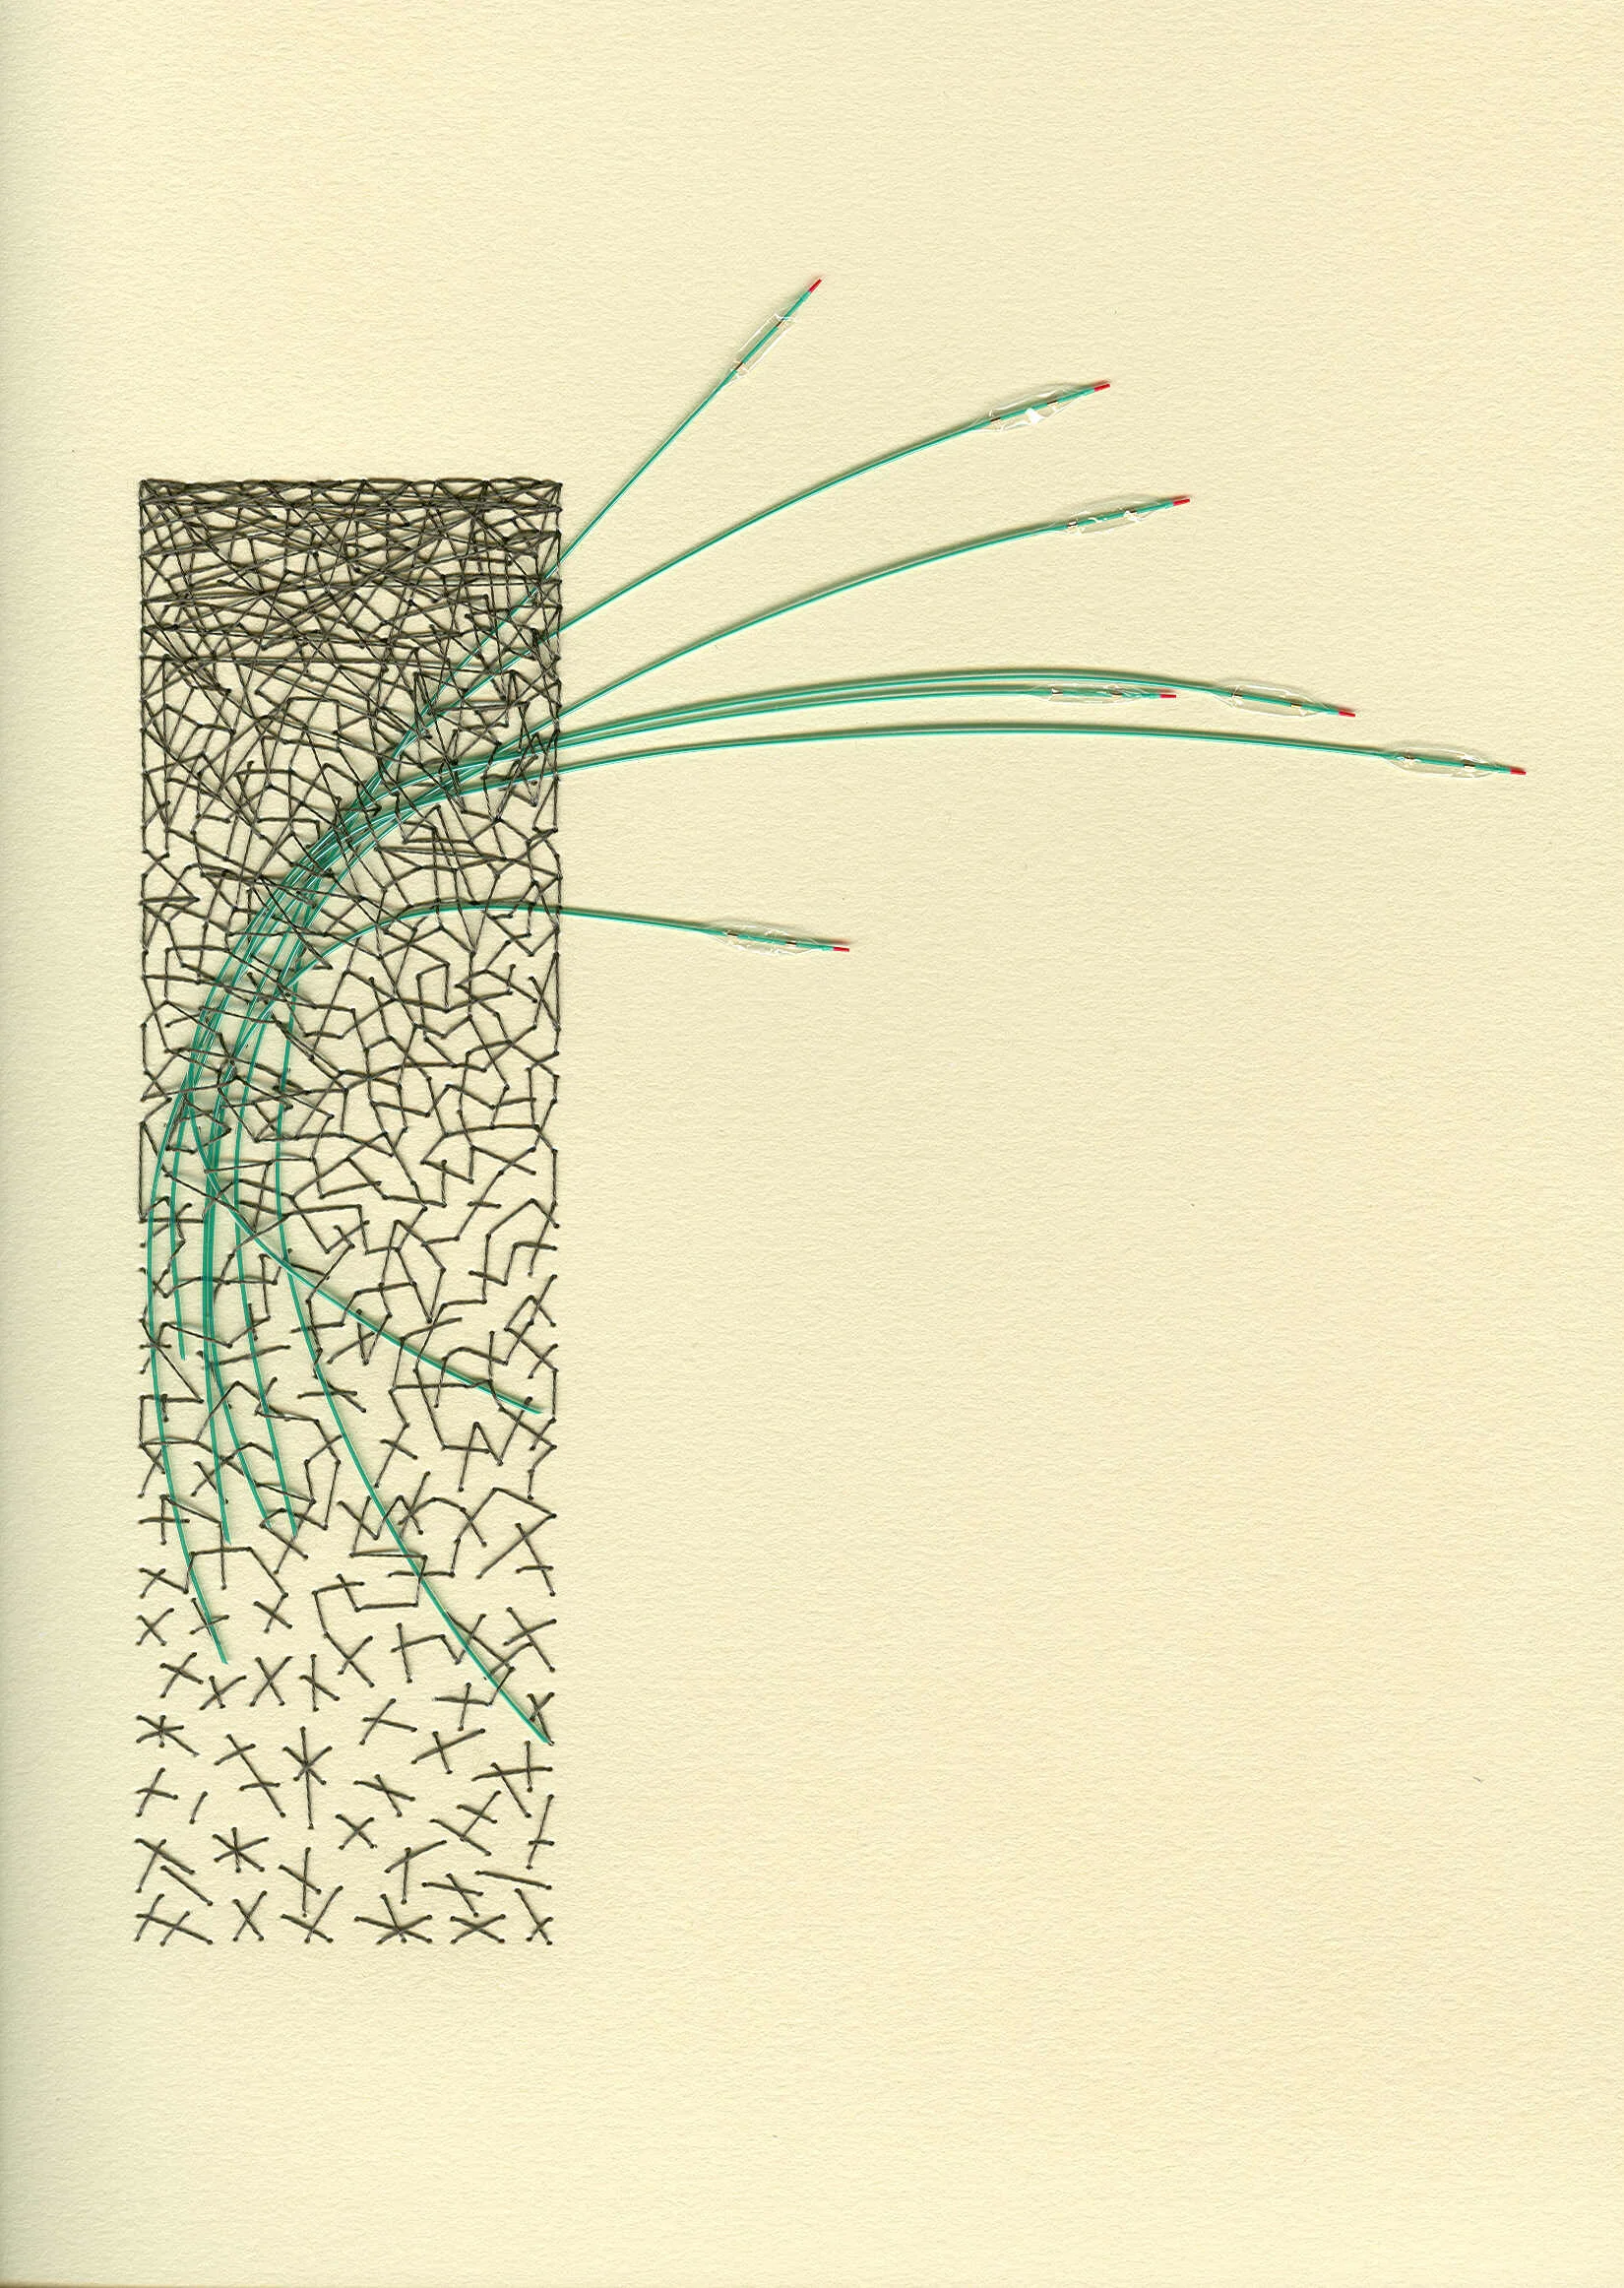

I’ve also had the pleasure of creating artwork for another corporate headquarter building based in MN. Boston Scientific commissioned me to create found object works that featured products which they created. You’ll see below some of those that feature angioplasty ports and balloons.

Chaos 3